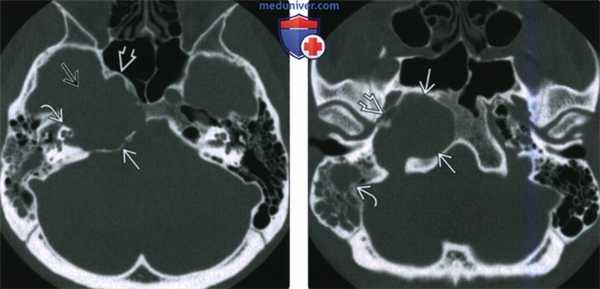

(Слева) При КТ в костном окне определяется распространенное образование с тотальной деструкцией передненаружного края. Образование распространяется в ВСК и приводит к эрозии слуховой капсулы. Кавернозный сегмент ВСА смещен кпереди.

(Справа) При аксиальной КТ височных костей (более каудальный срез) у этого же пациента визуализируется ХГ-ВП, сдавливающая костную часть евстахиевой трубы. Жидкость в сосцевидном отростке обусловлена обструкцией евстахиевой трубы.

(Слева) При аксиальной КТв костном окне в пневматизированной ВП слева визуализируется холестериновая гранулема в виде хорошо отграниченного экспансивного образования овоидной формы. Задняя стенка ВА истончена или отсутствует.

(Справа) При аксиальной МРТ Т1 у этого же пациента определяется гиперинтенсивный сигнал в левостороннем экспансивном образовании овоидной формы, сопоставимом с холестериновой гранулемой.